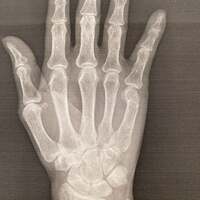

この日、小柳は「昨日受診した」「整形外科の院長先生の治療には感動しました!!」と述べ「救急外来で撮ったレントゲン写真」とレントゲン写真を公開。「小指第3関節の下綺麗に折れてる」「少し横から撮ると折れた骨が内側に入り込んでるのが分かります」とコメントし、レントゲン写真を見た医師から「このまま固めてしまうと握った時骨が出ず陥没した状態になり人前でお仕事をなさる方にはどうかな」と言われたことを明かした。

その後に更新したブログでは「右肘に麻酔の注射を打ち」「院長先生は」「画像をご覧になりながら折れてる骨を慎重にハメていかれました」と治療中の様子を報告。「レントゲン写真で確認」したといい「真っ直ぐになってる」と驚いた様子でつづり、治療後のレントゲン写真を公開した。